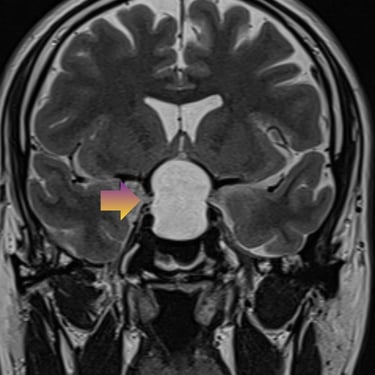

🧠Tumor selar quístico: abordaje mediante cirugía endoscópica transnasal (endoscopía selar).

Los tumores selares quísticos, como los adenomas hipofisarios quísticos o quistes de la bolsa de Rathke, pueden generar alteraciones visuales y hormonales. La cirugía endoscópica transnasal es una técnica mínimamente invasiva que permite el acceso seguro a la región selar, favoreciendo una resección eficaz con menor morbilidad.